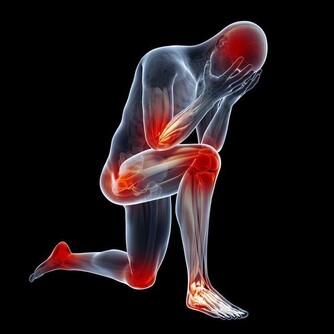

為了加強療效,防止損傷皮膚,在施推拿術時可選用一定的藥物作潤滑劑,如滑石粉、香油、按摩乳膏等。若局部皮膚破損或有骨折、結核、腫瘤、出血等症狀,禁止在不適部位做推拿保健。